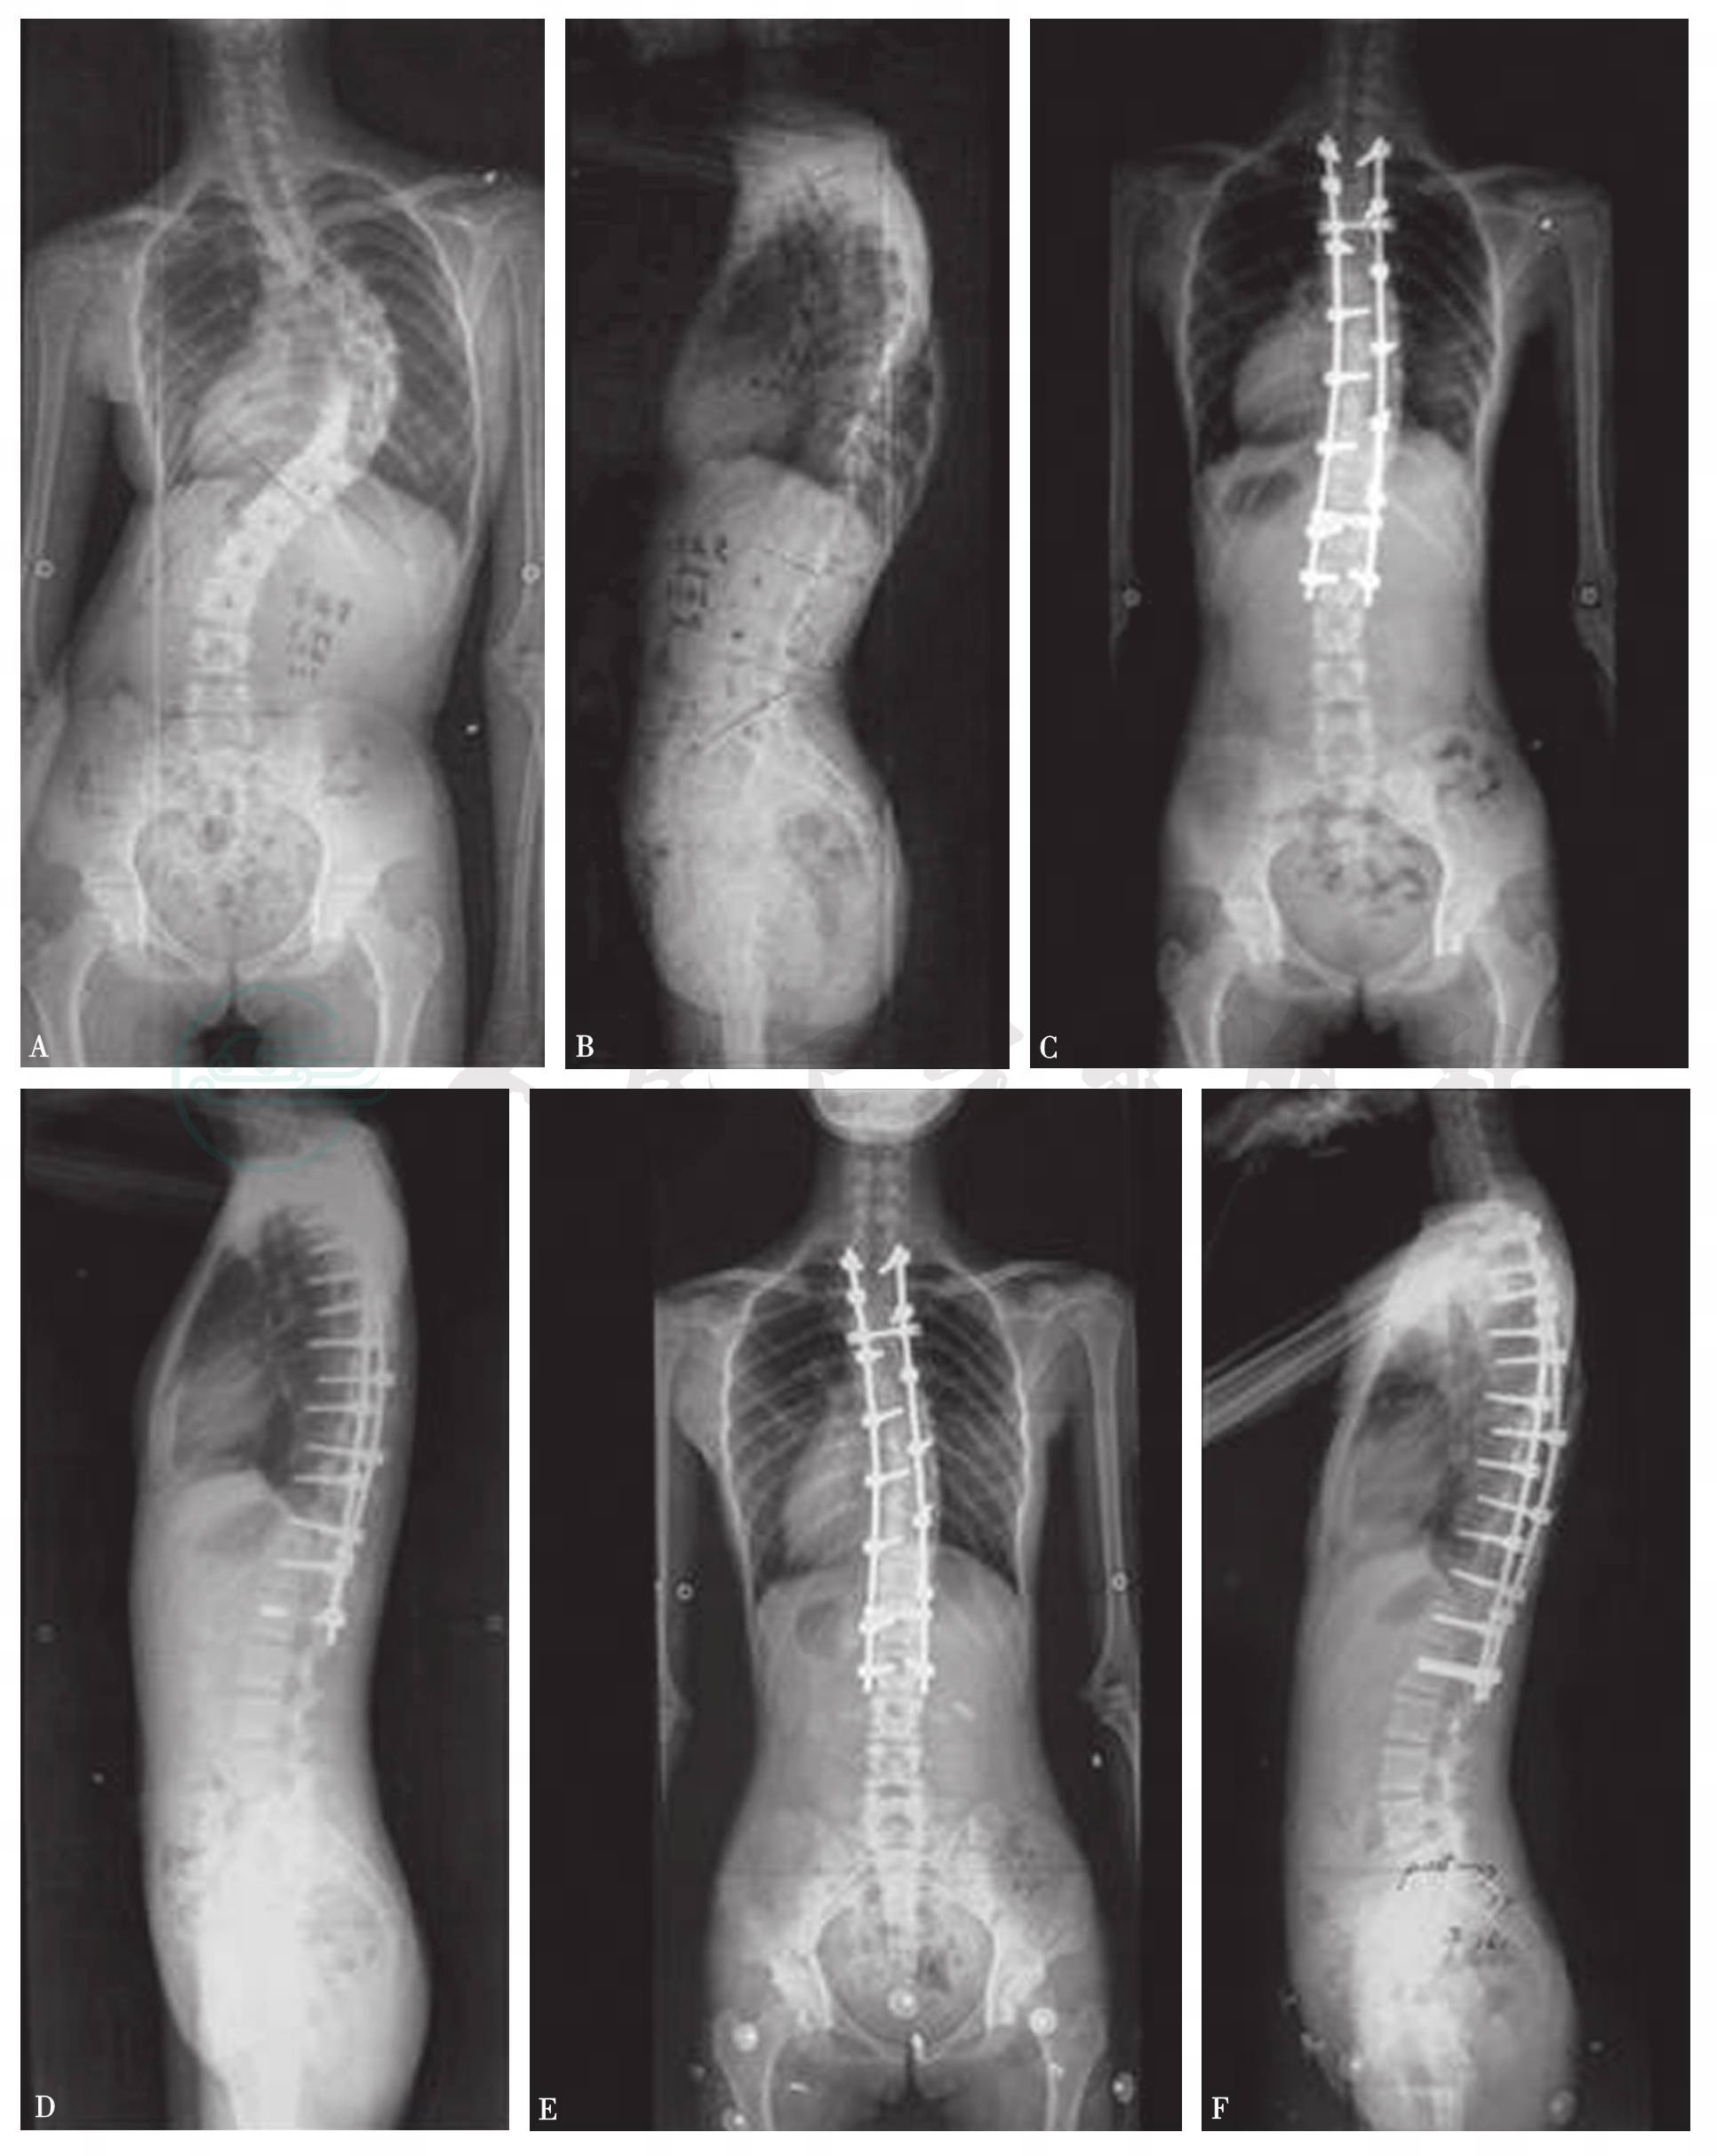

图25 女,14岁,AIS Lenke1AN型(A、B);术前Cobb角86°,行后路选择性融合术,术后矫形效果良好,Cobb纠正到25°(C,D),术后1年冠状面和矢状面矫形满意(E、F)

图26 女,13岁,AIS Lenke1B-型(A、B);术前Cobb角71°,行后路选择性融合术术后即刻矫形效果良好Cobb纠正到25°(C、D),术后2年冠状面和矢状面矫形满意(E、F)